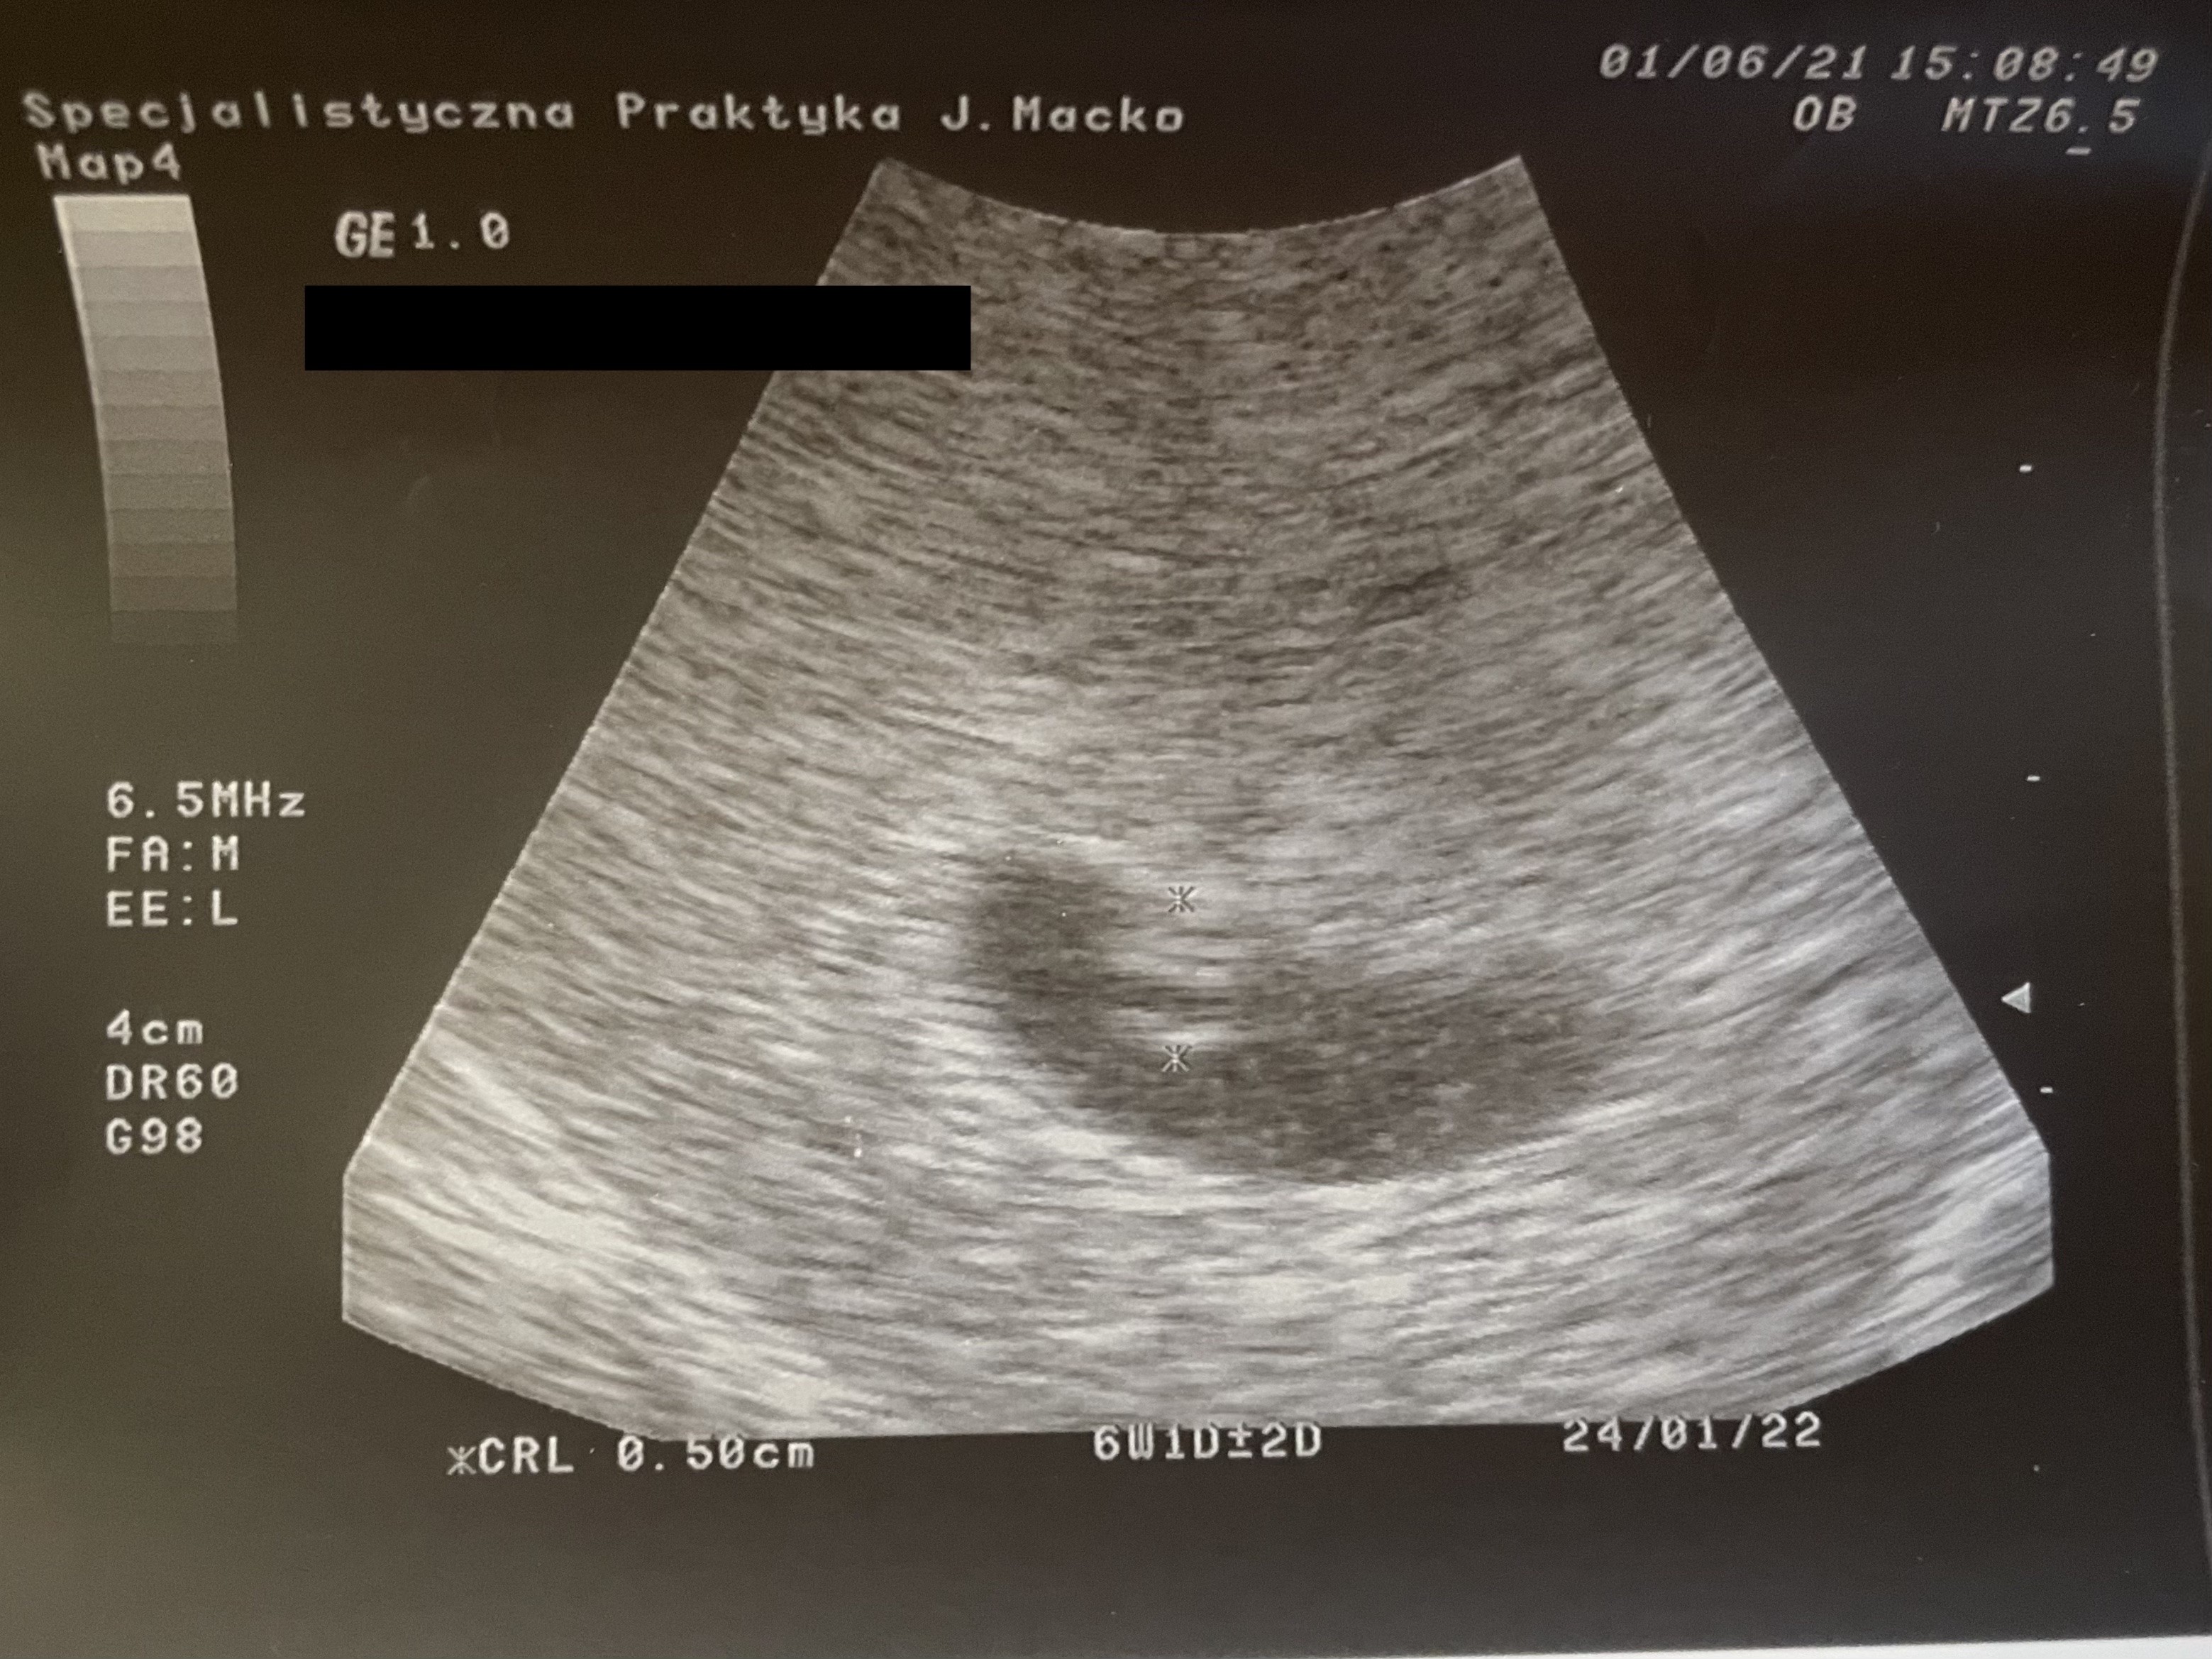

Dziewczyny, ale mi skrzacik zrobił niespodziankę na Dzień Dziecka! Ciąża starsza niż myślałam, dziś już 6t1d i uwaga, widziałam serducho! 😍 Pięknie biło 😍 Skrzacik ma całe 0,5 cm. 😁 Lekarz powiedział, że przyszłam w idealnym momencie, że to pierwsze dni bicia serduszka. W związku z tym termin mi się przesunął z 30 stycznia na 24.01 - @Klauuudia proszę o zmianę w pierwszym poście. Jedynie co to dostałam Duphaston, bo mi się cysta zrobiła na jajniku z którego owulacja była, więc to jest do kontroli i tyle. Następna wizyta za 2 lub 3 tygodnie, zależy tylko ode mnie. ☺️ Wrzucam zdjęcie (wymazałam tylko bardzo profesjonalnie nazwisko 😎🤣).